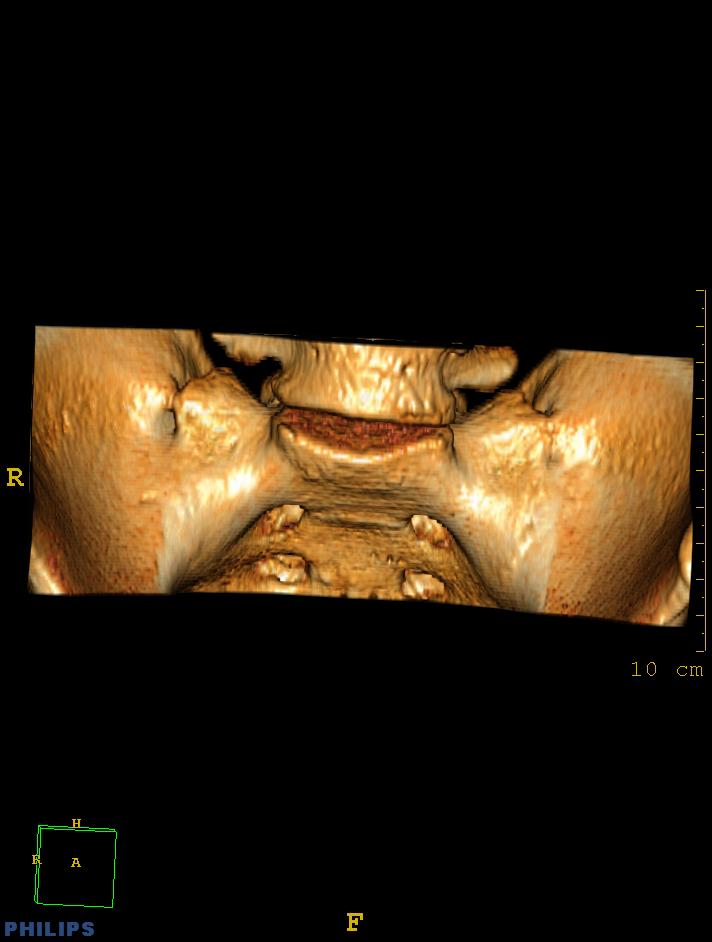

标题: CT14032:M34Y,双侧骶髂关节 [打印本页]

标题: CT14032:M34Y,双侧骶髂关节

m,34岁,腰痛三年,腰椎活动度明显减低,x片示腰椎竹节样改变

双侧骶髂关节骨性融合,软骨下囊性变,结合脊柱竹节样改变,典型的强直性脊柱炎。